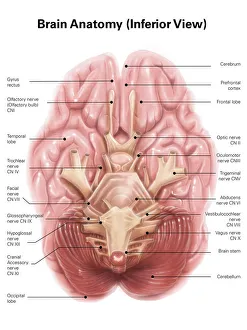

The central nervous system, the intricate network that governs our every thought and movement, is a marvel of complexity. From the delicate cerebellum tissue to the detailed light micrograph capturing its essence, we are reminded of its importance in maintaining balance and coordination. Anatomy comes alive as we explore the human brain from an inferior view. The intricacy of brain fibers is revealed through DTI MRI scans like C017/7099 and C017/7035, showcasing their vital role in transmitting information throughout this extraordinary organ. Artistic renderings bring us closer to understanding the medulla oblongata's significance within the brain. Its portrayal in various artworks allows us to appreciate how it controls essential functions such as breathing and heart rate. As we delve deeper into studying the central nervous system, models of the human brain provide invaluable insights into its structure and organization. Lateral views reveal countless regions responsible for cognition, emotion regulation, sensory perception, and motor control. Microscope slides offer glimpses into nerve cells' intricate architecture—a testament to their ability to transmit electrical signals at lightning speed. Meanwhile, glial stem cell cultures captured under a light microscope remind us of their crucial role in supporting neuronal function. Finally, artistic representations unveil the limbic system's enigmatic nature—an interconnected web responsible for emotions and memory formation. These captivating artworks allow us to visualize this complex network within our brains. Exploring these hints provides a glimpse into the awe-inspiring world of our central nervous system—the very foundation upon which our thoughts, actions, memories reside—reminding us just how remarkable our brains truly are.